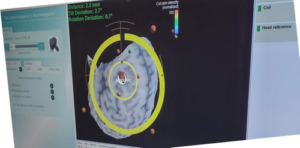

The TMS is an extremely interesting experience to me. They hook up this stretchy headband with sensors around my forehead and put me in front of a special two-eyed camera sensor and “show the camera” where my head is in space by touching the nose and each ear with their little electronic gizmos (image 2 below shows a bit of the headband as well as the paddle looking device which contains the magnetic coils inside.) Once the machine can identify the ears and nose, the technicians take a pencil-like device and trace a bunch of lines over the contours of the skull. It’s a little difficult to describe, but if you want to see the process, I found an older video from 2019 that shows a similar machine and you can see what I mean here.

All this technology helped to map out where my head was in the physical space in front of the camera. The camera is a dual lens device that has a long neck and if you can remember the character "WALL-e" from the movie, you'll have kind of an idea what that looks like. All these traced marks were overlaid on top of the MRI images they had loaded into the computer and helped them to aim the magnetic field to the very precise spot in my brain called the dorsal lateral prefrontal cortex. (Image 1 above.)

Top arrow indicates the TMS Coil pulse emitter in the technician’s hands. Bottom arrow indicates the sensor on the headband that the technicians use to “show the camera” where my head is in space –it’s used in conjunction with a pencil-like device which they touch the nose and each ear with to register me in space in front of the camera so it can ‘see me correctly”.